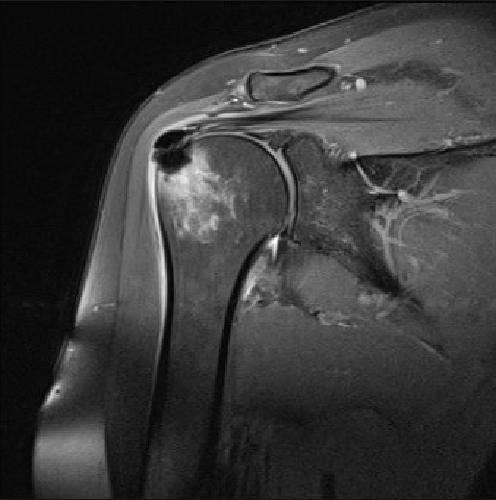

För att visa att jag inte bara pratar – här är mina MR-resultat före och efter.

Artros, artrit eller osteoporos är inte alltid lätta att känna igen – och med åldern drabbas nästan alla. Efter 50 års ålder har 93 % av människor tecken på degenerativa förändringar i broskvävnaden. Det är nästan omöjligt att helt skydda sig från ledproblem. I den här artikeln beskrivs ett fall av artros i axelleden – en särskilt komplicerad form, eftersom leden ligger djupt under musklerna och är svår att påverka direkt.